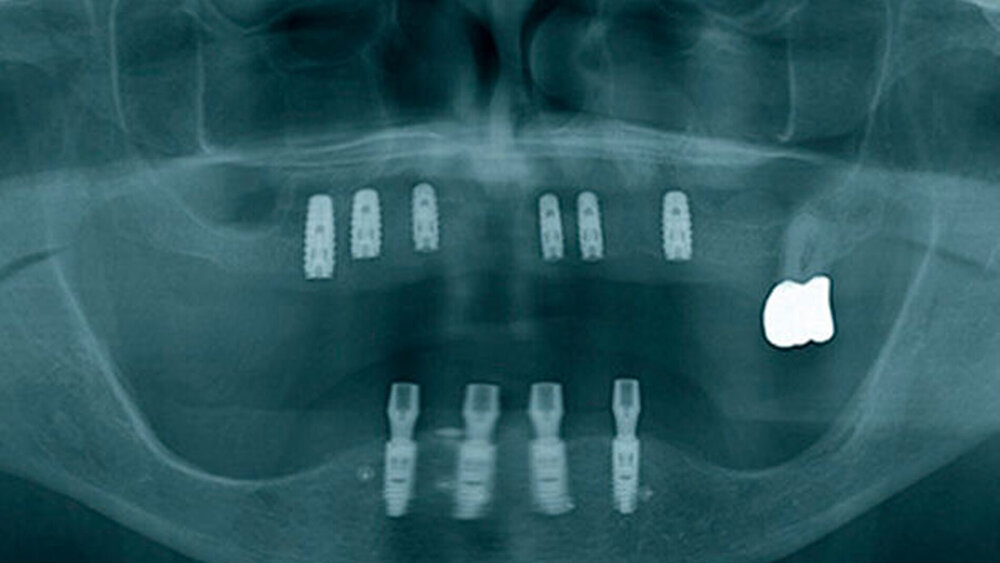

Eine 67 Jahre alte Patientin stellte sich mit dem Wunsch einer Oberkiefersanierung in unserer Praxis vor. Ihre Restzähne waren aufgrund von Parodontitis und funktioneller Überlastung nicht mehr erhaltungswürdig. Wir ließen sie bis kurz vor der definitiven Versorgung als strategische Pfeilerzähne für die Interimsprothese in situ.

Die dreidimensionale Positionierung und die richtige Anordnung der Implantate sowie des Zahnersatzes. Es ist wichtig, eine prächirurgische prothetische An- und Sprechprobe (Set-up) durchzuführen, um die Implantatpositionen und -achsen korrekt nach der späteren Prothetik zu bestimmen und auszurichten.

Das hat nichts mit den unterschiedlichen Protokollen zu tun. Der Übergang zwischen Restauration und dem Abutment darf nicht sichtbar sein, egal bei welchem Protokoll. Entweder werden die Implantate deshalb tiefer gesetzt oder der Knochen wird abgetragen. Unproblematischer ist das im Unterkiefer, die Lippe und die Lippenbänder verdecken viel. Wir implantieren – wann immer das geht – erst in der 3er-, 4er-, 5er-Position, nicht direkt in der Front.